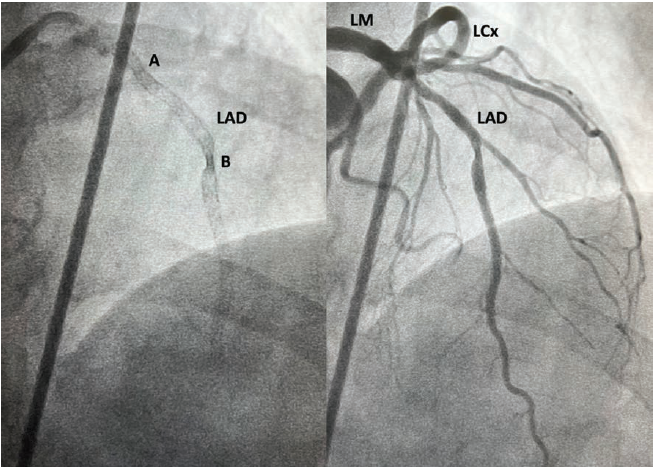

A 76-year-old female with a history of hypertension had a non-ST-elevation myocardial infarction and underwent percutaneous coronary intervention to a heavily calcified and severe diffusely diseased lesion from the proximal to mid LAD. No intravascular imaging was performed to guide the intervention. The proximal to mid LAD was predilated with a 2.25 mm semi-compliant balloon. The mid LAD was stented with a 2.25 mm x 38 mm drug-eluting stent (DES). The proximal portion of the stent did not fully expand due to calcification, but this was not recognized. Next, a 2.5 mm x 30 mm DES was deployed from the proximal to mid LAD, overlapping with the first stent by approximately 10 mm, such that there were 2 layers of stent that were under-expanded due to calcium in the mid LAD. Unfortunately, the interventionalist mistook the under-expanded segment for a lesion in the LAD that was missed and deployed a 2.5 mm x 12 mm DES in that segment. Finally, a 2.75 mm x 12 mm DES was deployed in the proximal LAD (Figure 1). The patient was discharged home the next day.

Three months later, the patient was referred to us with complaints of persistent Canadian Cardiovascular Society 3 angina despite optimal medical therapy and a nuclear stress test showing anterior wall ischemia. She was taken to the cardiac catheterization lab where angiography showed undersized and under-expanded stents in the proximal to mid LAD, including an area of severe stent under-expansion in the mid LAD with 3 layers of stents (Figure 1).

We planned on using the OPN NC super high-pressure balloon (SIS Medical AG) to expand the under-expanded stents. We attempted to perform optical coherence tomography (OCT) (Abbott Cardiovascular) of the LAD, but were unable to cross the more proximal area of stent under-expansion in the mid LAD (Figure 1, Letter A) with the OCT catheter. Next, we attempted pre-dilating, but despite a 7-French (F) extra backup 3.5 guide catheter, 7F guide extension catheter, and extra support guidewire, no balloon could be delivered across that lesion. We therefore performed laser atherectomy with an 0.9 mm laser (Philips) at 80 fluence and 80 pulses per second for a total treatment time of 180 seconds, facilitated by concomitant administration of 70% contrast to cross the proximal and mid lesions (Figure 1, Letters A and B). After laser atherectomy, we pre-dilated the LAD with a 2.5 mm x 20 mm semi-compliant balloon up to 20 atmospheres (atm). OCT of the LAD was performed, which despite pre-dilation, showed a minimal stent area (MSA) of 1.19 mm2 (Figure 2). We attempted to expand the lesion with a 2.5 mm x 12 mm noncompliant (NC) balloon at 22 atm, but this showed a significant waist (Figure 3). Dilation with a 3.0 mm x 10 mm OPN NC super high-pressure balloon at 35 atm, however, resulted in complete expansion of the under-expanded segment of stents (Figure 3). The remainder of the LAD was post-dilated with 4.0 mm and 3.5 mm NC balloons up to 20 atm. OCT was performed again, showing good stent expansion and an improvement in the stent area at the more distal lesion from 1.19 mm2 to 4.50 mm2 (Figure 2). Final angiography also showed a significant improvement in expansion of the LAD stents (Figure 4).